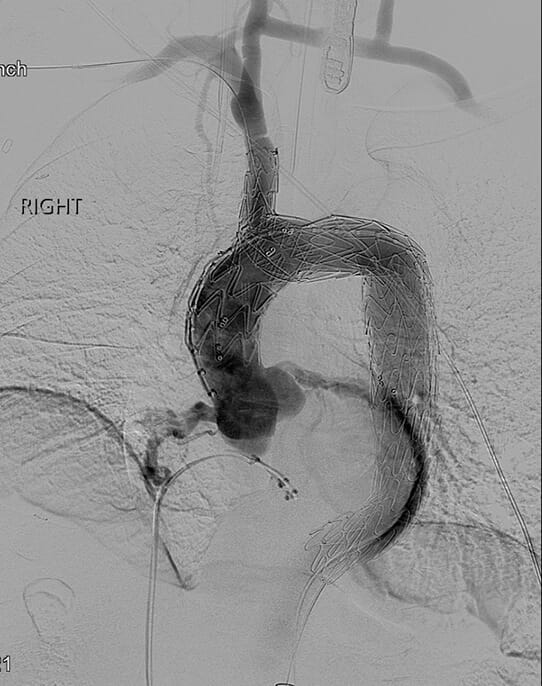

- Endovascular repair with Nexus aortic arch stent graft system - In stage one, the surgeon uses open techniques through a small incision in the neck to reroute cerebral and upper extremity blood flow by bypassing from the right carotid artery to the left carotid artery and the left subclavian artery. This technique avoids the need for open-chest surgery. Two to three days later, incisions in the groin enable deployment of the stent graft into the aortic arch and into the ascending aorta with a side branch graft into the innominate artery. Patients are typically able to return home a couple of days later.

The Nexus stent graft configurations are engineered to accommodate a range of anatomies and can be adjusted for the length and diameter of the ascending innominate artery and descending aorta. Stable anchoring of the deployed stent graft provides a durable and lasting repair, while the minimally invasive procedure reduces risk of postoperative complications. Additional benefits include procedural consistency, efficient healthcare resource utilization, reduced risk of infection and improved patient comfort.